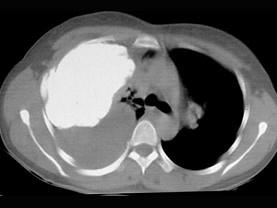

问题 男,66岁,剧烈胸痛,请结合CT图像,选择最可能的诊断 ( )

选项 A、右侧肺不张 B、右侧肺肺癌 C、右肺癌侵犯胸膜 D、右侧胸膜间皮瘤 E、右侧胸腔积液胸膜钙化

答案 D